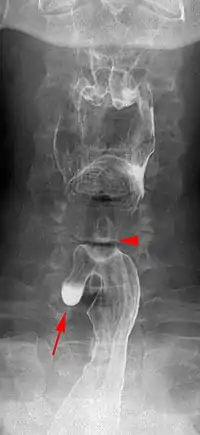

Killian–Jamieson diverticulum. The arrowhead points at the closed upper esophageal sphincter, arrow points at the diverticulum partly filled with contrast medium.

A Killian–Jamieson diverticulum is an outpouching of the esophagus just below the upper esophageal sphincter.[1]

The physicians that first discovered the diverticulum were Gustav Killian and James Jamieson. Diverticula are seldom larger than 1.5 cm, and are less frequent than the similar Zenker's diverticula. As opposed to a Zenker's, which is typically a posterior and inferior outpouching from the esophagus, a Killian–Jamieson diverticulum is typically an anterolateral outpouching at the level of the C5-C6 vertebral bodies, due to a congenital weakness in the cervical esophagus between the oblique and transverse fibers of the cricopharyngeus muscle. It is usually smaller in size than a Zenker's diverticulum, and typically asymptomatic.[2] Although congenital, it is more commonly seen in elderly patients.[3]